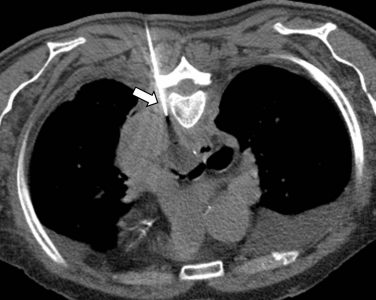

Σε έναν δεύτερο πυλώνα ογκολογικής θεραπείας η Επεμβατική Ακτινολογία μπορεί να εφαρμόσει τοπικοπεριοχική θεραπεία καταστροφής των καρκινικών κυττάρων με τεχνικές είτε διαδερμικής κατάλυσης (Ablation) είτε διαδερμικού ενδαγγειακού χημειοεμβολισμού (TACE). Στην περίπτωση της κατάλυσης μπορεί να εφαρμοστεί σε καρκινώματα του ήπατος, του νεφρού, των οστών και των όγκων μαλακών μορίων και υπό προυποθέσεις στον πνεύμονα. Παθοφυσιολογικά βασίζεται στην τοπική καταστροφή των καρκινικών κυττάρων με τη δημιουργία ιδιαίτερα υψηλών θερμοκρασιών νέκρωσης εντός του όγκου. Αυτό επιτυγχάνεται με τοποθέτηση ειδικών βελονών-ηλεκτροδίων εντός του όγκου υπό ακτινολογική καθοδήγηση. Τα ηλεκτρόδια αυτά παράγουν υψηλή θερμοκρασία είτε με τη βοήθεια ραδιοσυχνοτήτων (RF ablation) είτε με τη βοήθεια μικροκυμάτων (MW ablation) και προκαλούν πηκτική νέκρωση των καρκινικών κυττάρων χωρίς να επηρεάζουν τα φυσιολογικά κύτταρα.